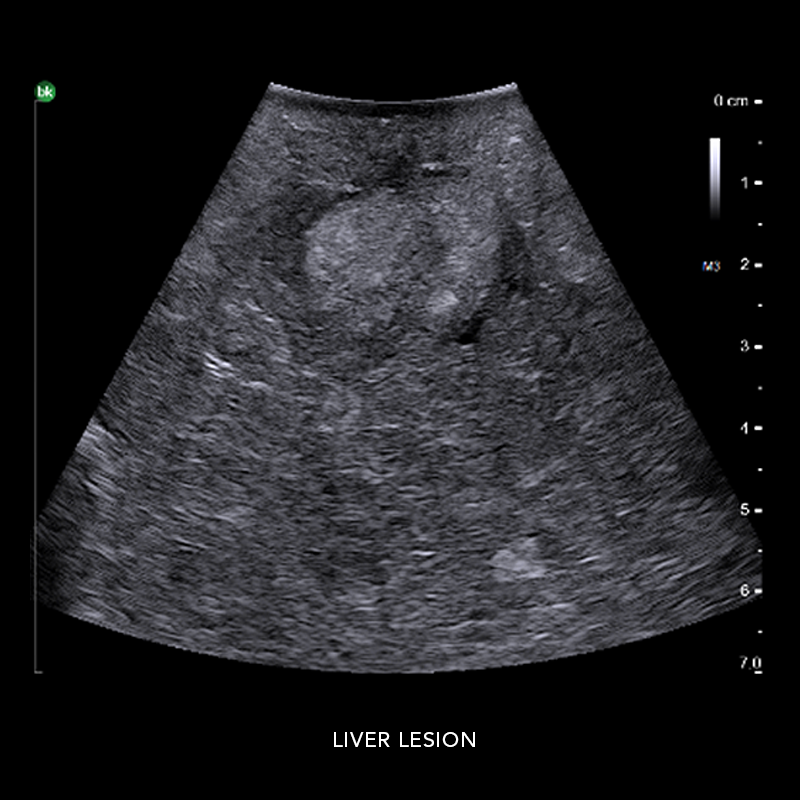

www.hiclipart.comUltrasound Stock Illustration - Image: 66373327

www.hiclipart.comUltrasound Stock Illustration - Image: 66373327

dreamstime.comultrasound blank generic display screen illustration stock

dreamstime.comultrasound blank generic display screen illustration stock